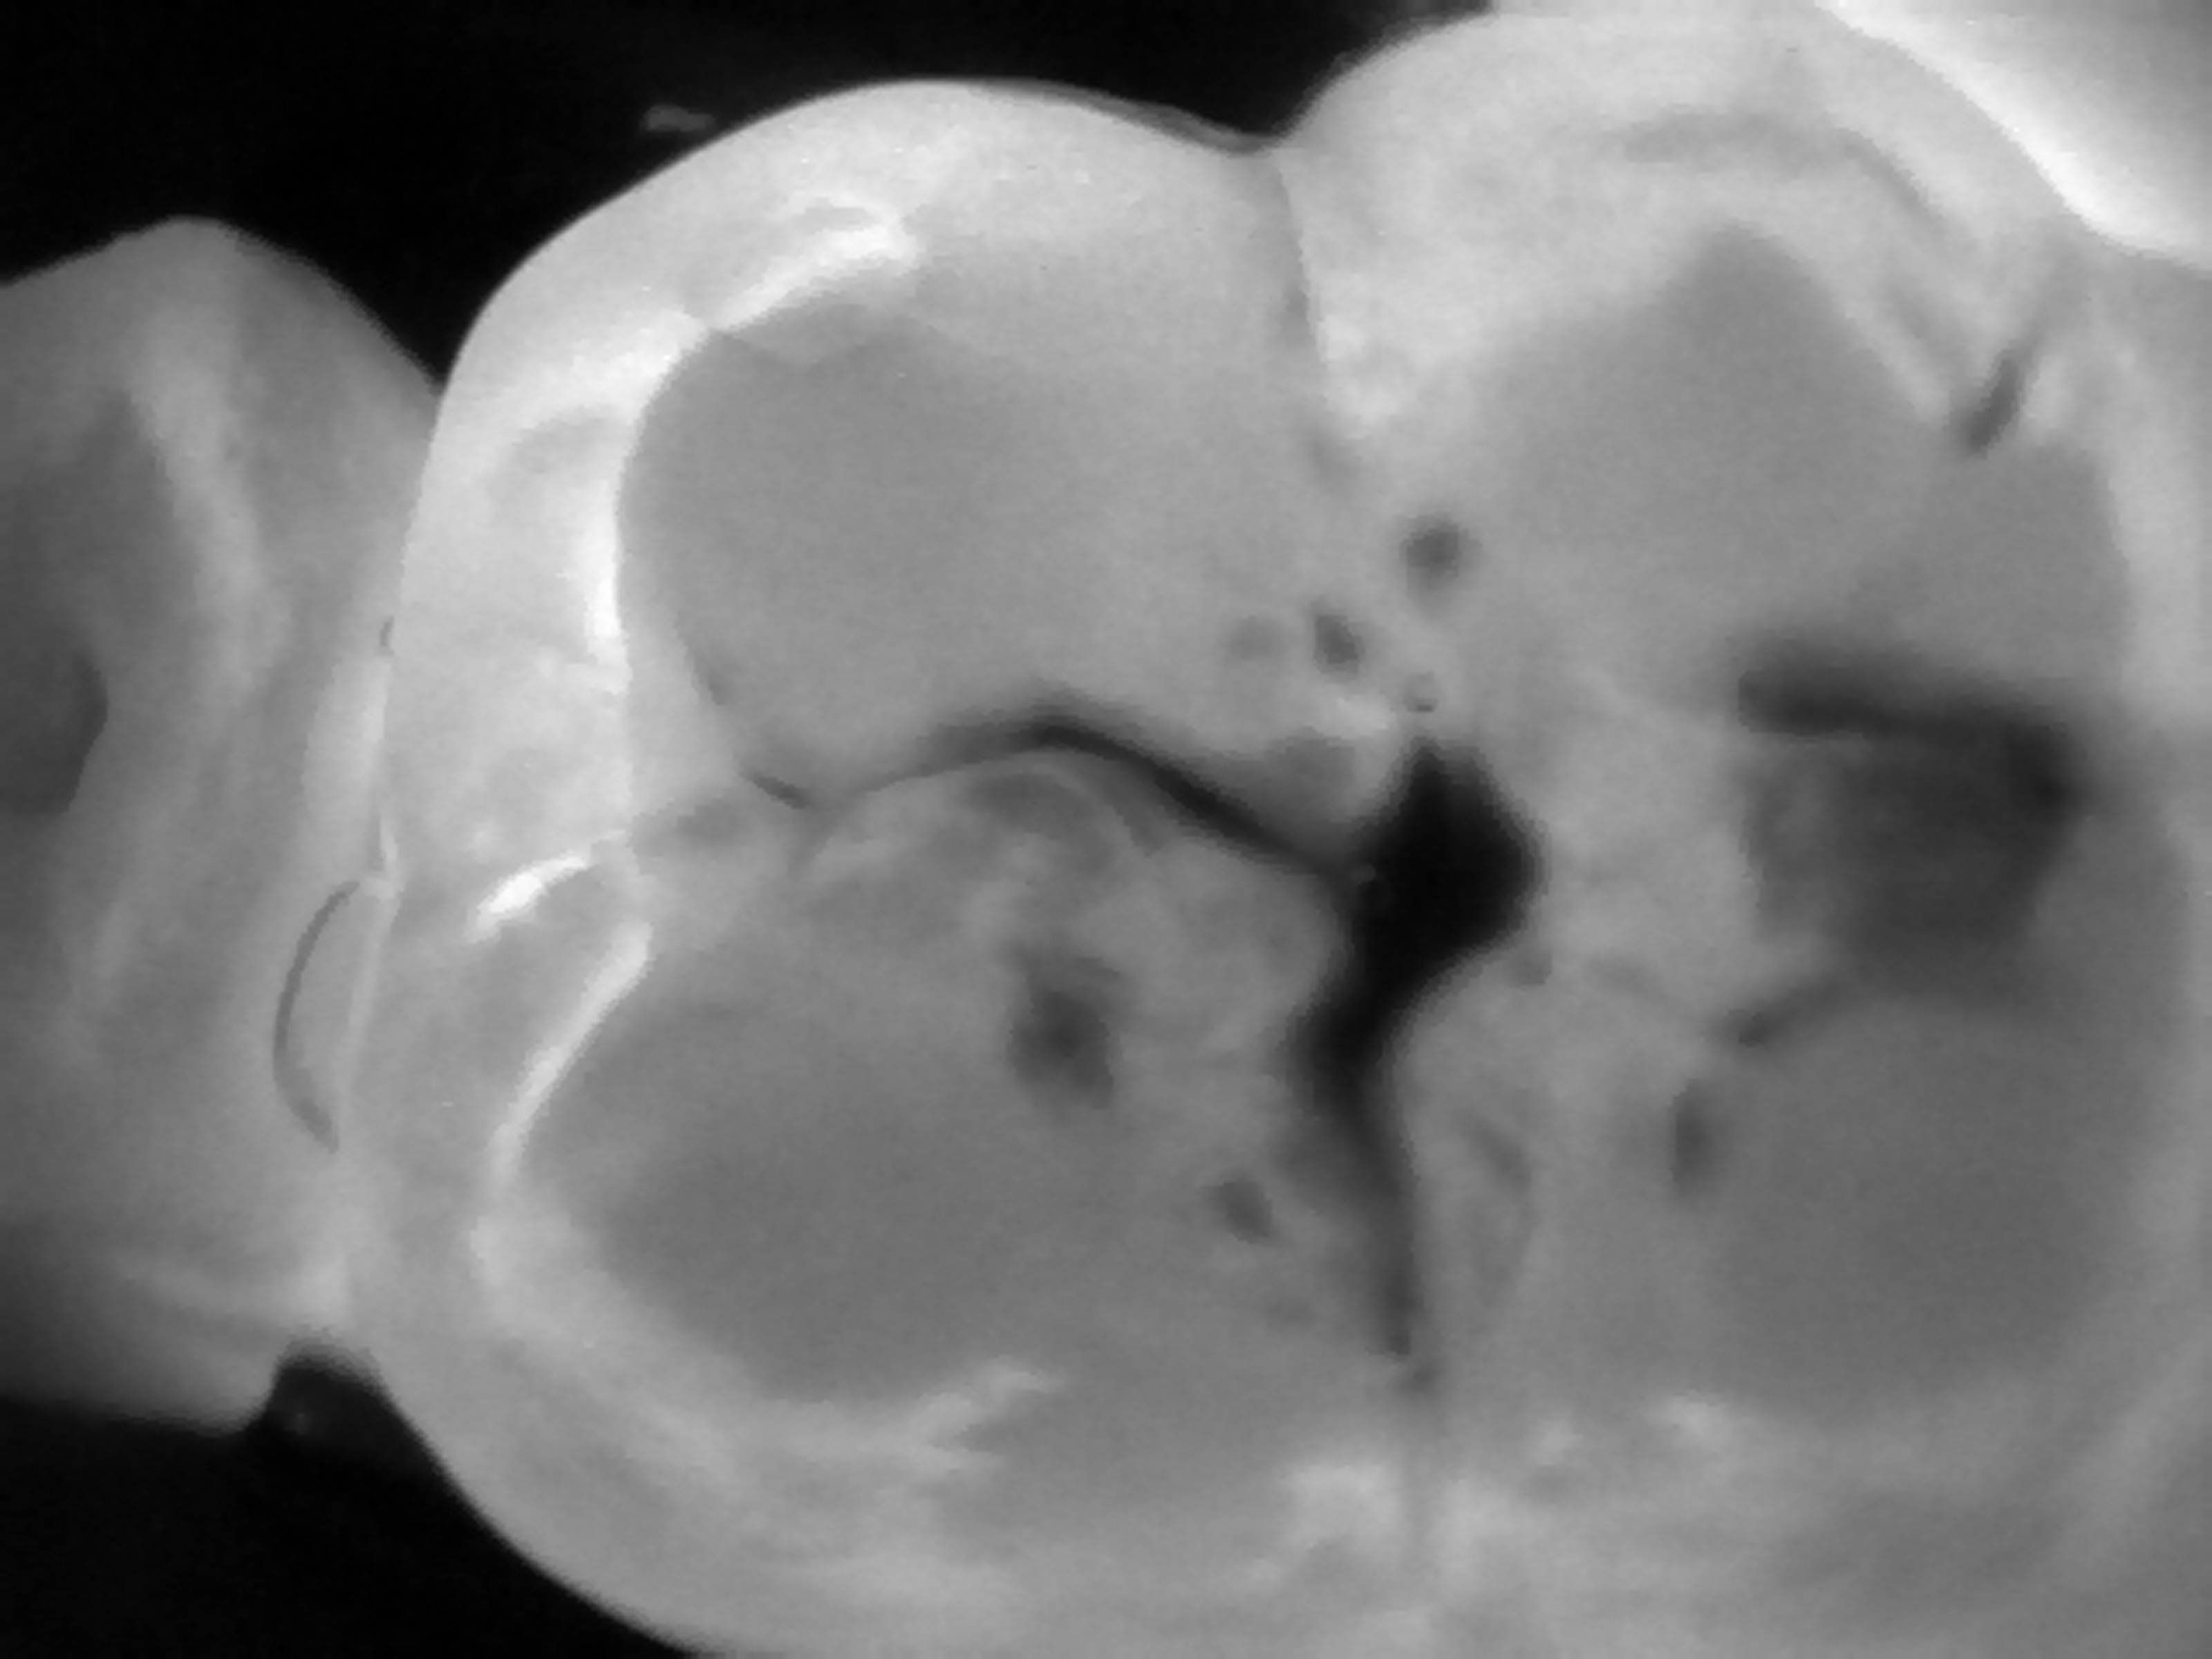

Zdjęcie lub film z badania danego zęba jest analizowane przez lekarza dentystę w poszukiwaniu wszelkich zaciemnień powierzchni, które będą wskazywać na obecność zmiany próchnicowej. Na powierzchni okluzyjnej będą to nieregularne plamy, zlokalizowane najczęściej w okolicy bruzd zębów, wykazujące penetrację próchnicy pod szkliwo. Na powierzchniach stycznych będą to ciemne miejsca w kształcie trójkątnym lub trapezowym, szerszą ścianą skierowane w stronę zewnętrznej powierzchni szkliwa, a węższą ścianą (w przypadku trapezu) lub ostrym kątem (w przypadku trójkąta) w stronę zębiny, lub wręcz stykającą się z obrysem zębiny. Im szerszy jest kontakt tej ciemnej powierzchni z obrysem zębiny tym bardziej zaawansowany jest ubytek próchnicowy na powierzchni stycznej.

Obraz prześwietlonego zęba trzonowego ze zmianą próchnicową na powierzchni okluzyjnej uzyskany w technologii NILT przy pomocy urządzenia DIAGNOcam (KaVo).